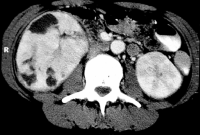

Von Wichtigkeit sind die bildgebenden Verfahren: Sonographie, CT bzw. AUR.

Beispielhaft die Darstellung eines ausgedehnten Nierenabszesses in Sonographie, CT und AUR (Abbildung 6).